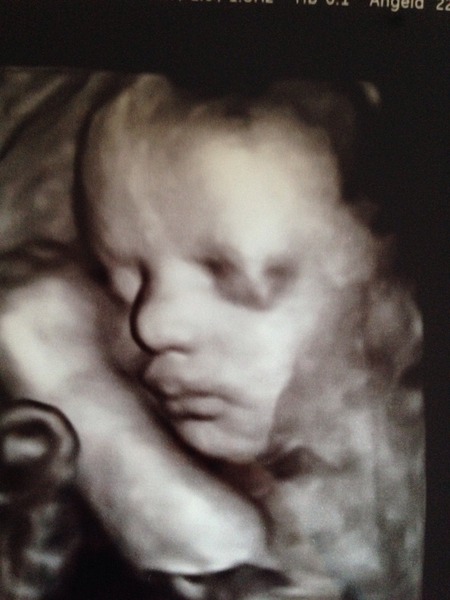

Now I had my 20 weeks scan done in 2 parts this time by 2 different people and they both said girl but I'm still not convinced after having 3 boys, we have a name picked out for both just incase.